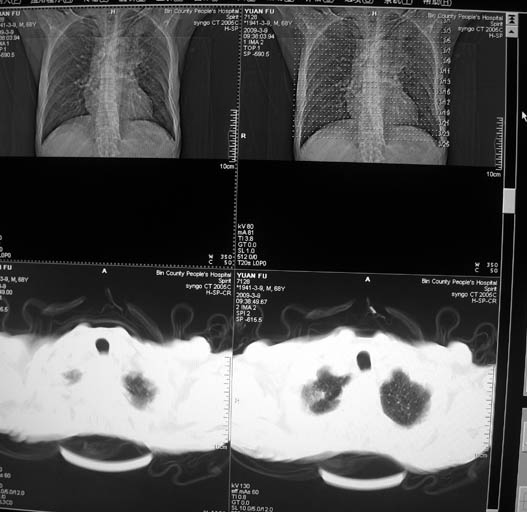

标题: CT18577:男,68岁,左肺占位。 [打印本页]

标题: CT18577:男,68岁,左肺占位。

男,68岁,左上肺占位,肺门淋巴结转移?

1)考虑左肺上叶尖段周围型肺癌并阻塞性肺炎,纵隔淋巴结转移。2)心包少量积液。

1)考虑左肺上叶尖段周围型肺癌并阻塞性肺炎,纵隔淋巴结转移。2)心包少量积液

1)考虑左肺上叶尖段周围型肺癌并阻塞性肺炎,纵隔淋巴结转移。

2)心包少量积液。